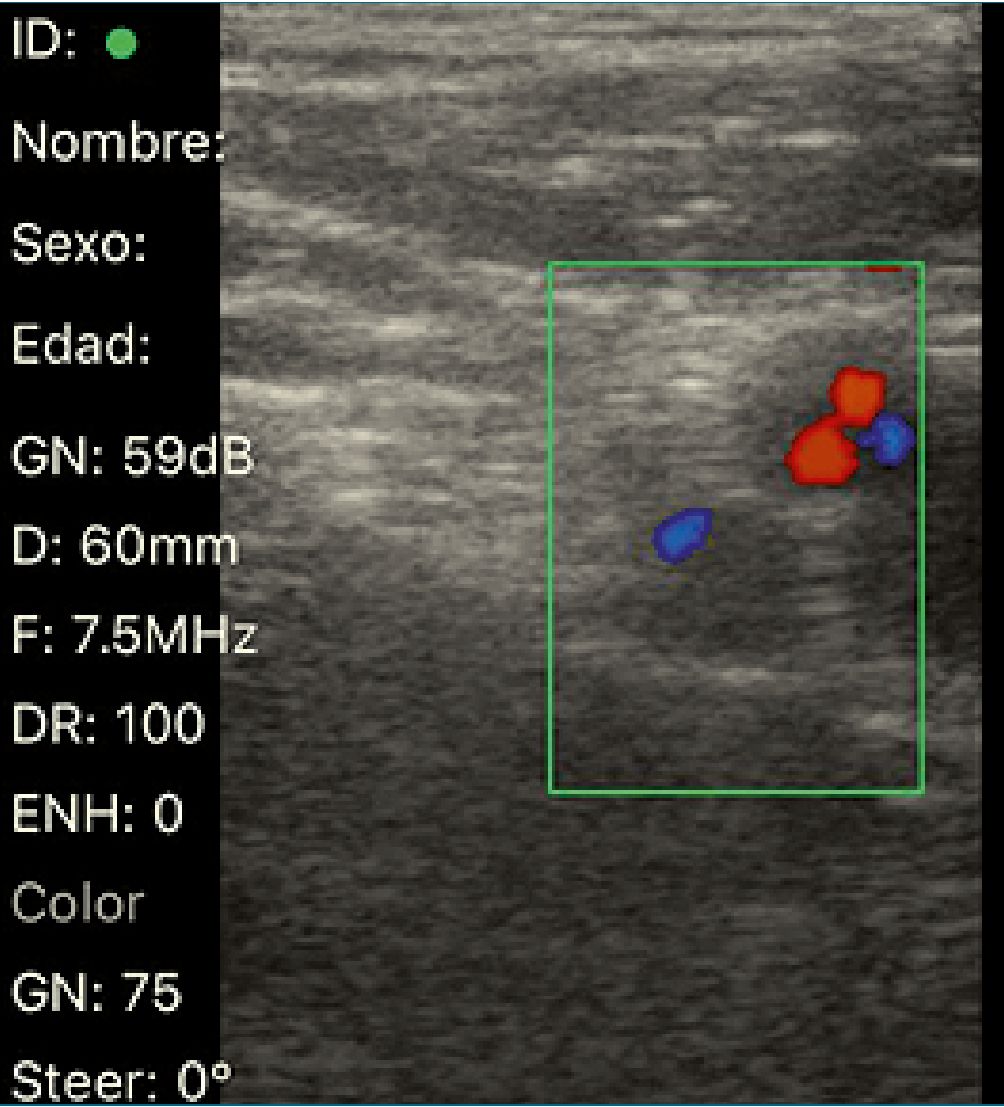

Descripción de la técnica de bloqueo femoral (Figura 1)

La sonda lineal se coloca justo debajo y paralela al ligamento inguinal. Usando una presión mínima del transductor para evitar el colapso de los vasos, el Doppler se usa para identificar la arteria ilíaca circunfleja superficial, ya que esta arteria pasa con frecuencia superficialmente al nervio femoral. La aguja se introduce en un plano desde la dirección lateral a la medial, con el objetivo de «hacer estallar» la fascia ilíaca a medida que se extiende sobre el nervio femoral[31],[32].

Figura 1. Bloqueo de nervio femoral guiado por ultrasonido.